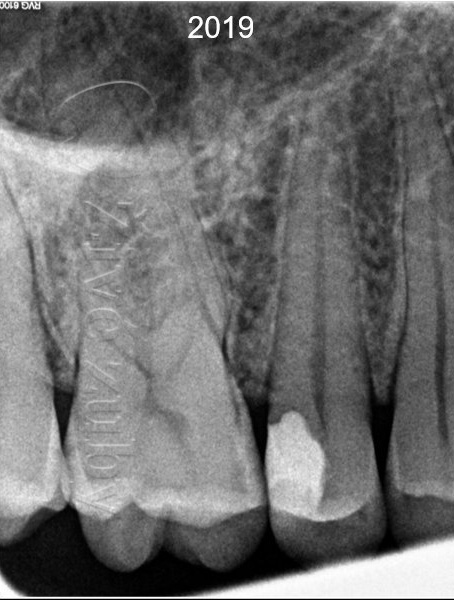

V roce 2006 nás navštívil dospělý pacient s hlubokým zubním kazem, který zasahoval do blízkosti zubního nervu (červená šipka na RTG snímku). Zub reaguje vitálně a pacient si stěžuje na citlivost při jídle.

Pokus o záchranu zubu se zachováním vitality. Obvykle k tomu postačuje zhotovení zubní výplně. Odhadovaná cena ošetření je cca 1000 – 2000Kč (dle rozsahu). První výplň bylo nutné vyměnit cca po 10 letech. V případě selhaní je záložní plán endodontické ošetření (viz varianta B).

Při pečlivém stanovení vitality zubu je úspešnost biologicky orientovaného ošetření vyšší ale i výrazně levnější. Jednoduší postupy jsou prediktabilnejší a dostupnější jak pro lékaře, tak i pro pacienta. Šetrný přístup z dlouhodobého hlediska má výhodný cost-benefit (šetří zuby pacienta i jeho peněženku). Odsunutí náročnějšího ošetření přináší výhodu modernější medicíny. Odklad jen o několik let přináší pokrok jak v materiálech, tak i dovednostech ošetřujícího lékaře. V případě selhání ošetření existuje záložní plán na záchranu zubu.